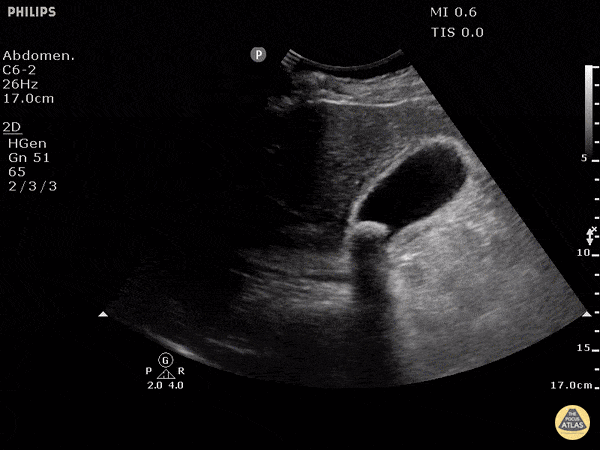

A biliary POCUS was performed, and showed the following:

This patient was found to have a positive sonographic Murphy’s sign, a stone in the neck of the gallbladder, and a thickened gallbladder wall. She was admitted to the surgical team and had an uncomplicated cholecystectomy the same day.